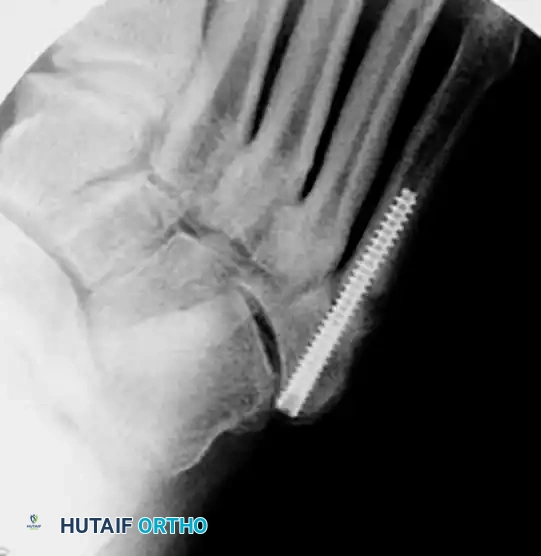

- Measurement: Estimate the length of the screw from the intraoperative radiographs. The screw must be long enough to bypass the fracture site and engage the diaphyseal isthmus, ensuring all threads are distal to the fracture line to allow for interfragmentary compression.

- Insertion: Place the screw over the guide wire. A 4.5mm to 5.5mm partially threaded screw is typically utilized, depending on the patient's canal diameter.

- Head Burial: It is imperative to countersink or bury the head of the screw into the tuberosity. A prominent screw head will cause severe irritation to the peroneus brevis tendon and overlying skin, often necessitating a second surgery for hardware removal.

- Verify final screw placement, fracture reduction, and compression with orthogonal radiographs.